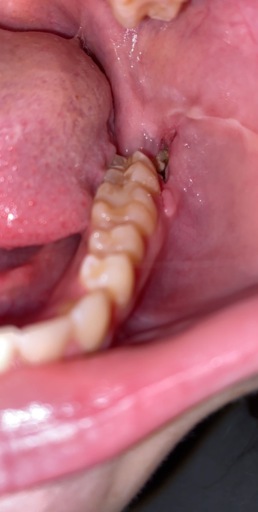

Teeth bent and twisted and a lot of pain given

For a long time I have been expriencing a lot of pain I'm my teeth when I eat drink and not do anything with them, when I eat I go through a lot of pain and feel sick and light headed because of it. My teeth are twisted and bent and one of them which is my adult tooth and another one which is my adult tooth feels like it's going to fall out which gives me more pain as they have been pushed backwards and forwards and I'm looking on some advice to do.